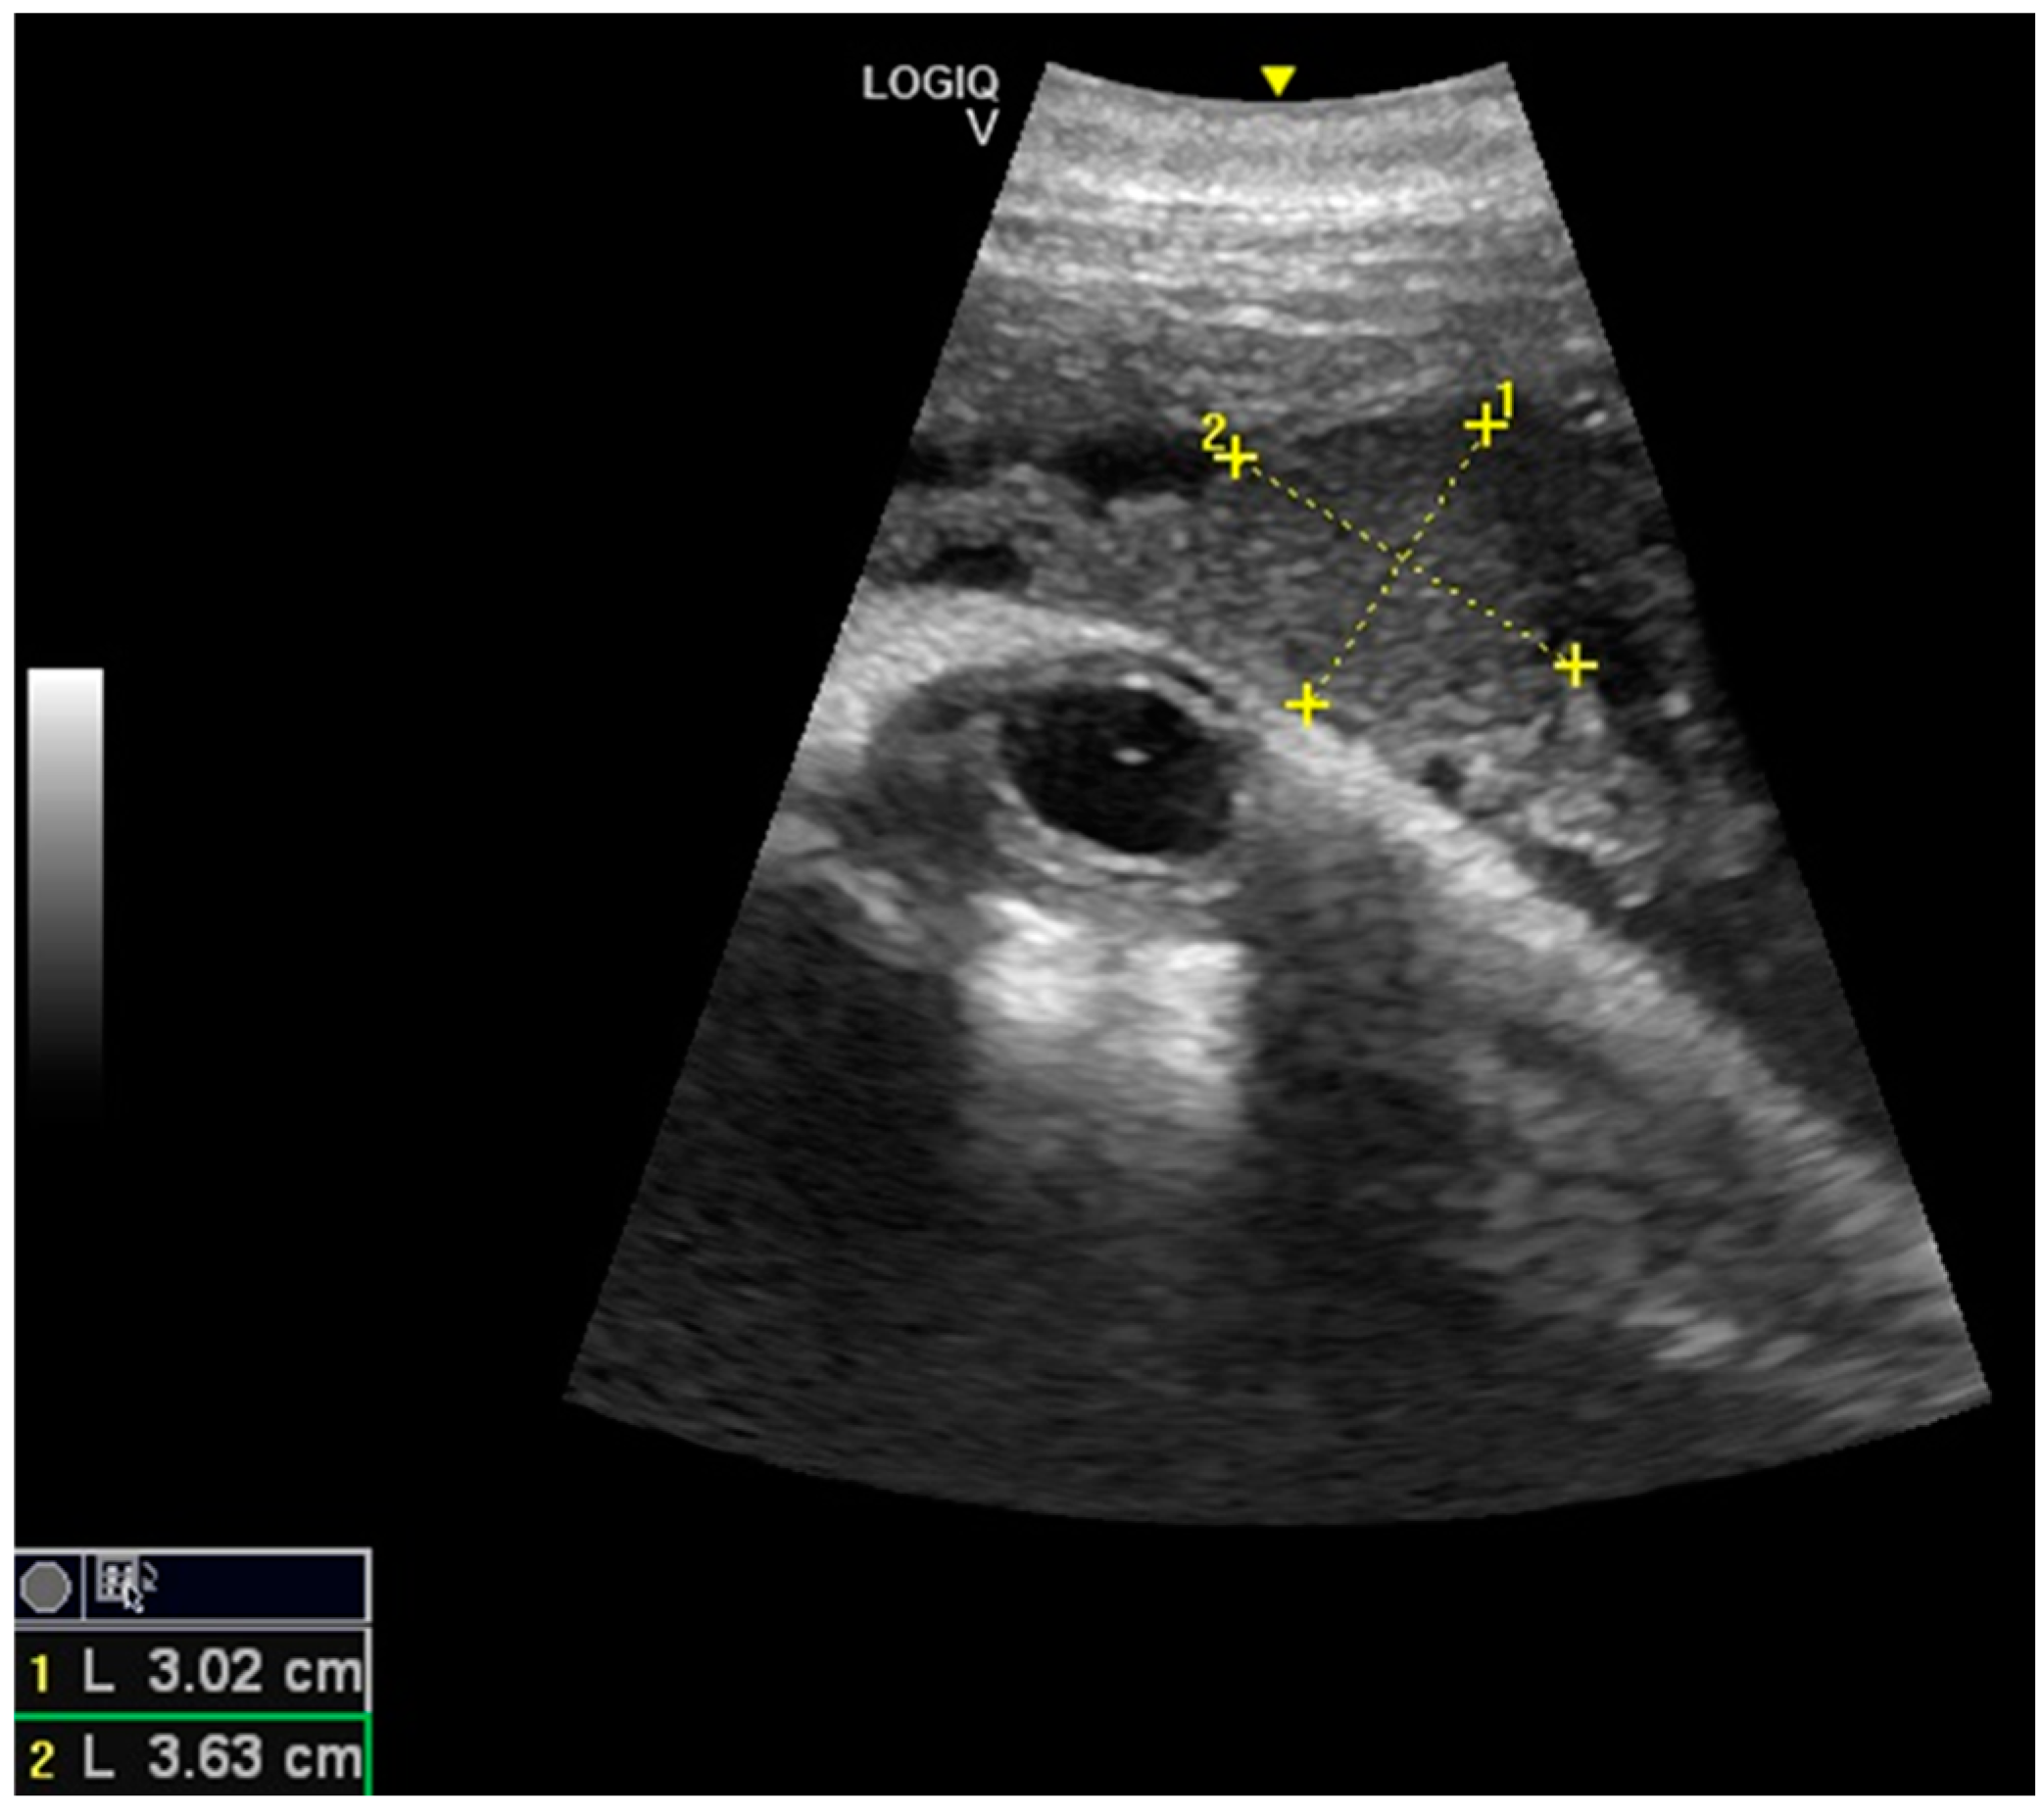

Considering the 16 pregnancies, the percentage of ovulation in the left ovary was 68.75%, whereas the ovulation in the right ovary was 31.25%, and it was of interest that two dams always ovulated in the right ovary. Maximum corpus luteum (CL) longitudinal diameter was 3.63 cm and transversal diameter was 3.02 cm (Figure 1), even though the diameter may vary according to laterality. The results concerning the gonadal activity correspond to previous studies [18,19,20].

Figure 1.

Corpus luteum (CL) with measurements.